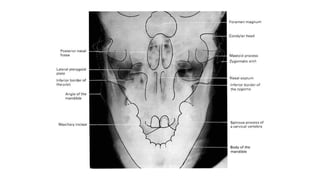

Occipitofrontal view

 This projection is used to demonstrate the frontal and

ethmoidal sinuses.

 It is also known as the Caldwell’s view.

 The patient is seated upright in front of the receptor and their

forehead and nose are placed against it.

 The beam is centred at around 15 to exit at the nasion.

⁰

• collimation

• lateral to the skin margins

• superior and inferior to the borders of the sinus cavities

Two frontal views of the skull demonstrate an incidental rounded, sclerotic lesion growing into the right frontal sinus (white arrows).

z Occipitofrontal view  Thisprojection is used to demonstrate the frontal and ethmoidal sinuses.  It is also known as the Caldwell’s view.  The patient is seated upright in front of the receptor and their forehead and nose are placed against it.  The beam is centred at around 15 to exit at the nasion. ⁰ • collimation • lateral to the skin margins • superior and inferior to the borders of the sinus cavities

Two frontal viewsof the skull demonstrate an incidental rounded, sclerotic lesion growing into the right frontal sinus (white arrows).